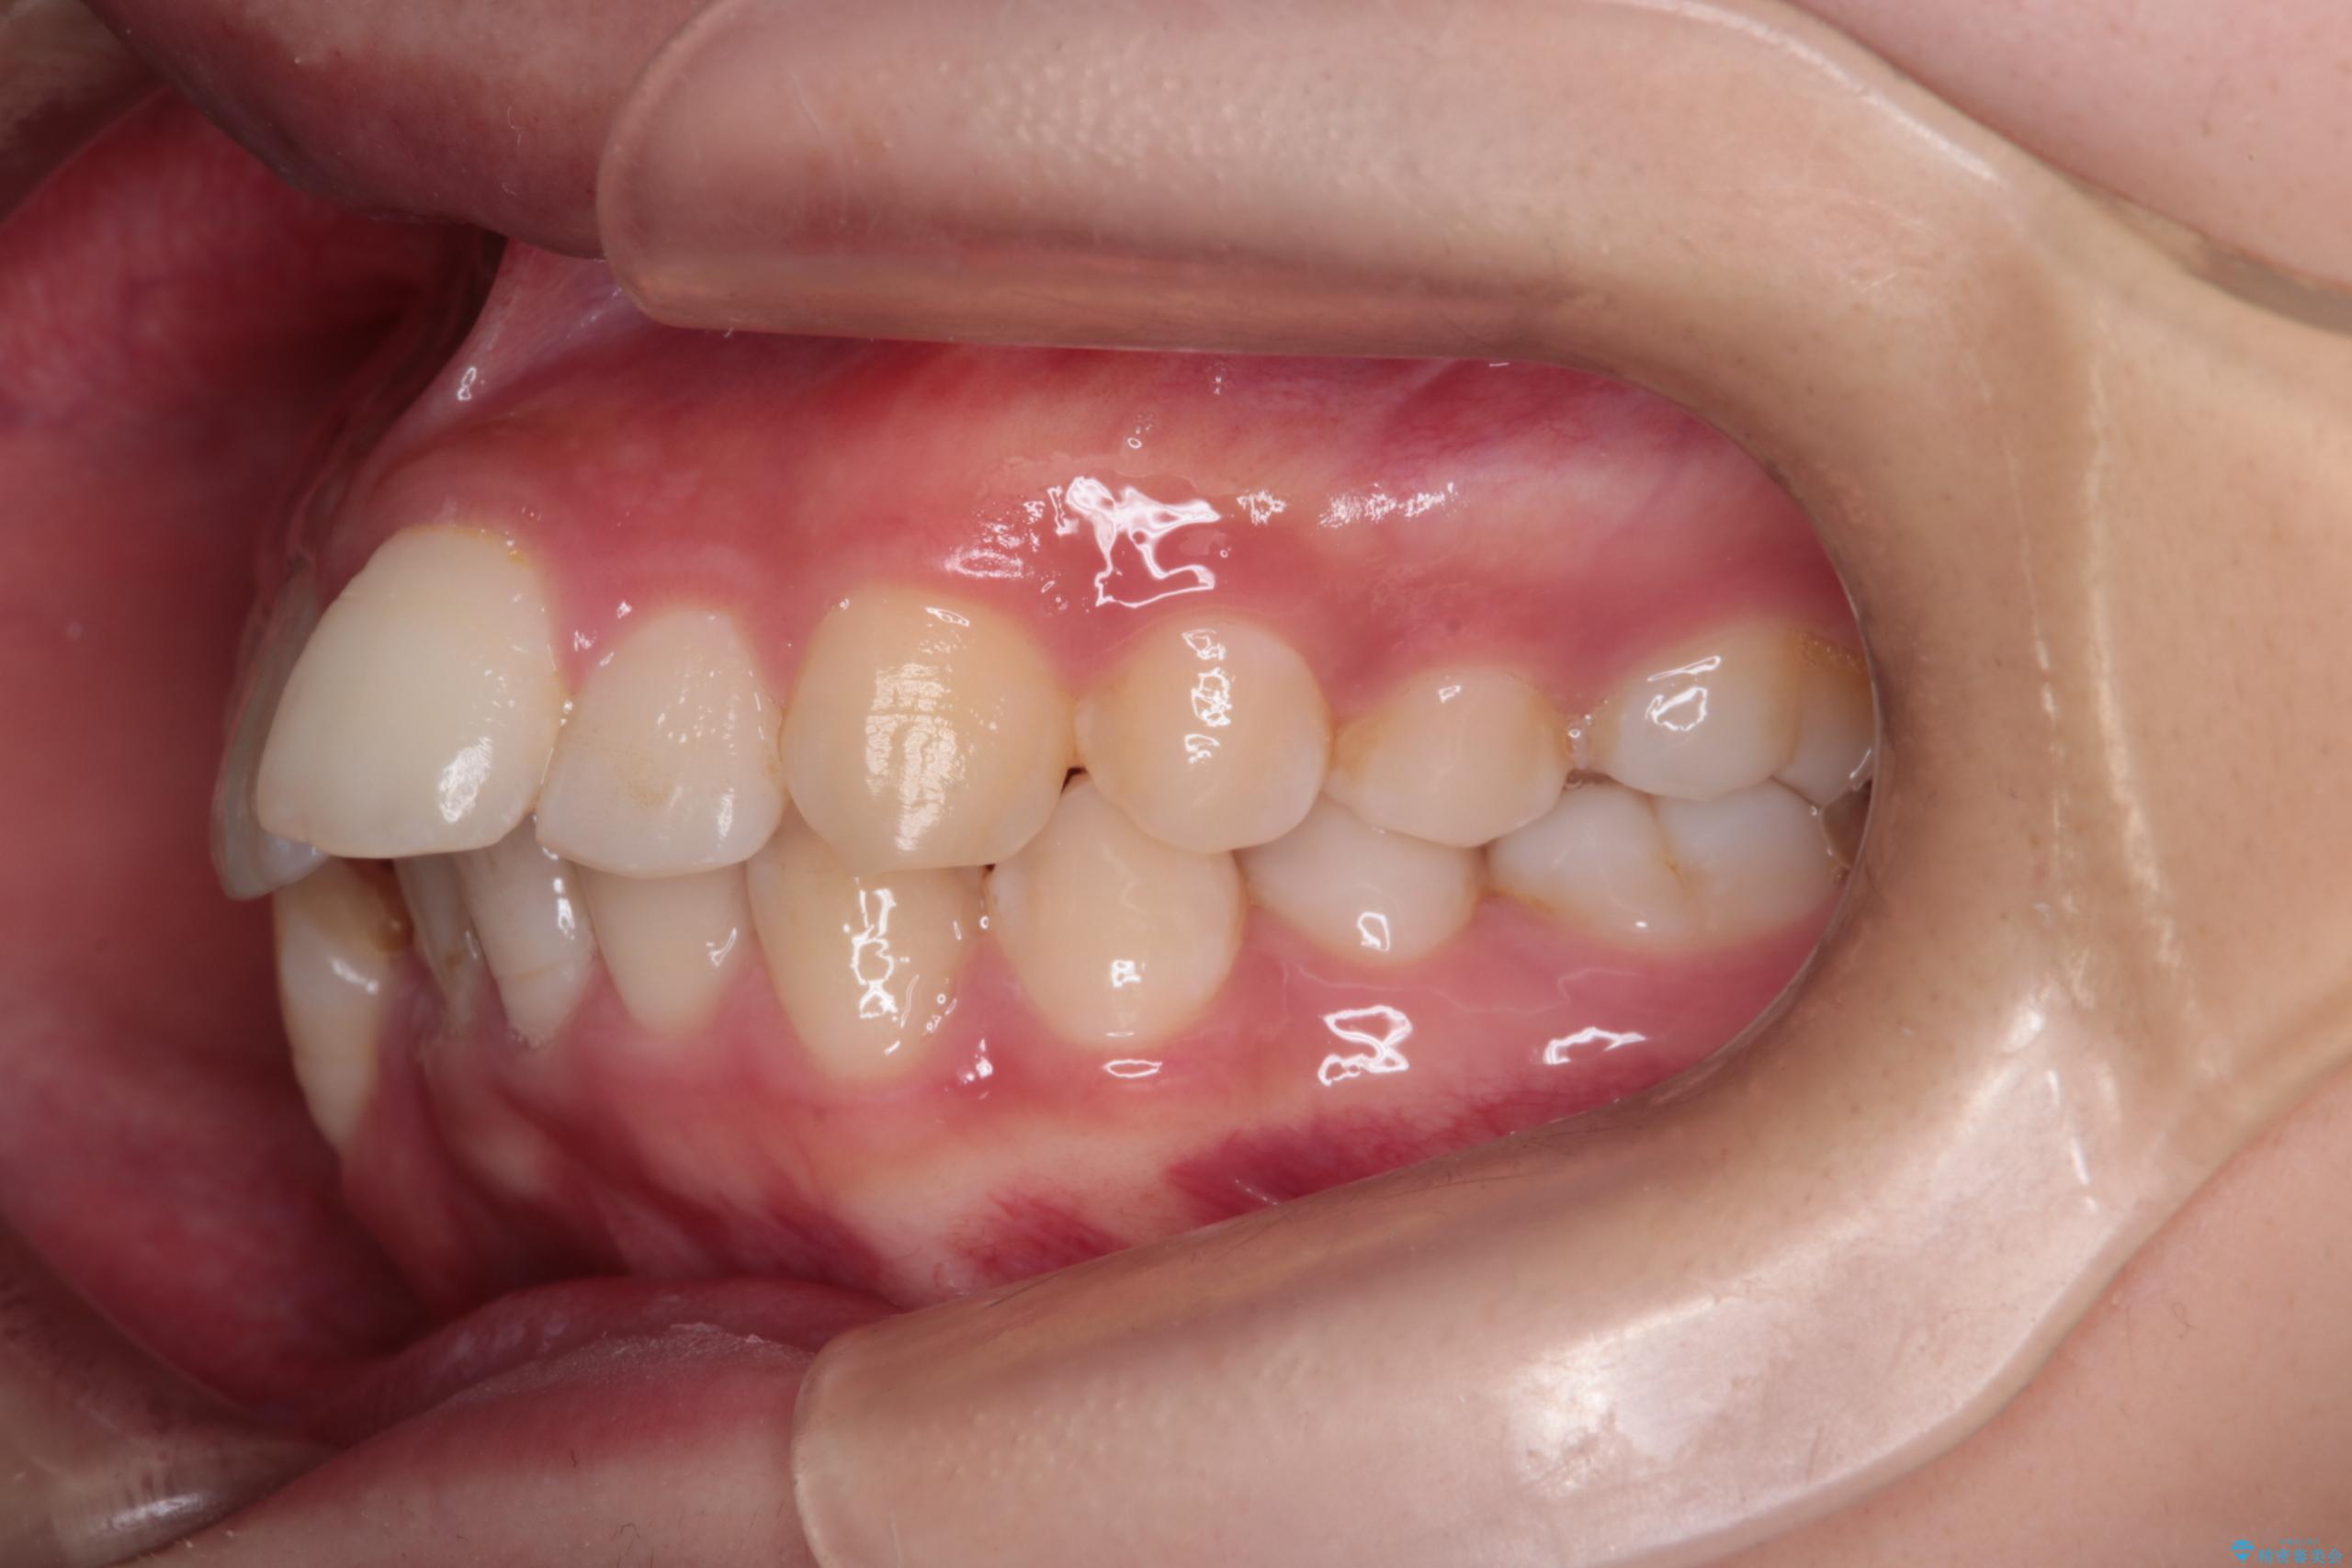

- 前歯から奥歯にかけて歯の重なりが激しい歯のがたつき(重度叢生)を主訴にご来院されました。精密検査の結果、歯が並ぶスペースが大幅に不足しており、歯並びを整え、口元を美しく引っ込めるためには、スペースの確保が必要と診断しました。そこで、上下左右の第一小臼歯(4番目の歯)を計4本抜歯し、そのスペースを利用して歯並び全体を整える抜歯矯正の治療計画を立案。装置には、透明で目立たないインビザラインを採用し、審美性と治療効果の両立を目指しました。

今回の治療では、重度の叢生を改善するため、まず計画通り上下左右4本の小臼歯を抜歯し、歯を並べるための十分なスペースを確保しました。装置には透明で取り外し可能なインビザラインを使用。抜歯によってできたスペースを最大限に活用し、マウスピースを定期的に交換しながら、デコボコを解消しつつ、前歯を効果的に後退させました。

治療の結果、長年の悩みであった重度の歯のがたつきが解消され、口元の突出感も改善。機能的にも安定し、審美的にも美しい、理想的な歯並びを獲得していただけました。